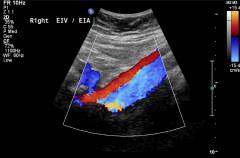

Неспецифический аортоартериит (болезнь Такаясу)

Неспецифический аортоартериит – хроническое заболевание, при котором развивается воспалительный процесс в аорте и отходящих от нее крупных сосудов. Реже поражение при заболевании может захватывать легочные артерии.

Заболевание, как и другие системные васкулиты, встречается редко. Женщины болеют в 3 – 8 раз чаще мужчин.

Хирургическое лечение неспецифического аортоартериита

Показания к хирургическому лечению неспецифического аортоартериита:

- значительное нарушение кровотока в почках;

- значительное нарушение кровообращения в головном мозге;

- нарушение кровообращения в конечностях, гангрена.

Обычно выполняется операция шунтирования – врач замещает пораженный участок сосуда на взятый из другой области тела или на искусственный имплантат.